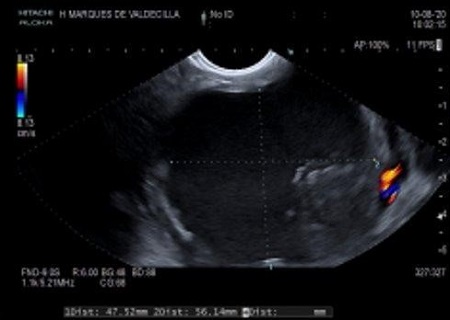

A las 72 h presentó febrícula y un difícil control del dolor, por lo que se realizó una TC abdominal que objetivó la formación de colecciones pseudoquísticas peripancreáticas (Fig. 1). Recibió tratamiento antibiótico endovenoso con ceftriaxona y metronidazol. Durante el seguimiento en las consultas de Gastroenterología Pediátrica se mantuvieron las colecciones quísticas con signos de pancreatitis necrotizante y compresión del confluente mesentérico-portal, por lo que finalmente se decidió drenaje guiado por ecoendoscopia mediante cistogastrostomía y colecistectomía programada tras su resolución, con buena evolución.

Figura 1. Colección peripancreática visualizada mediante ecoendoscopia